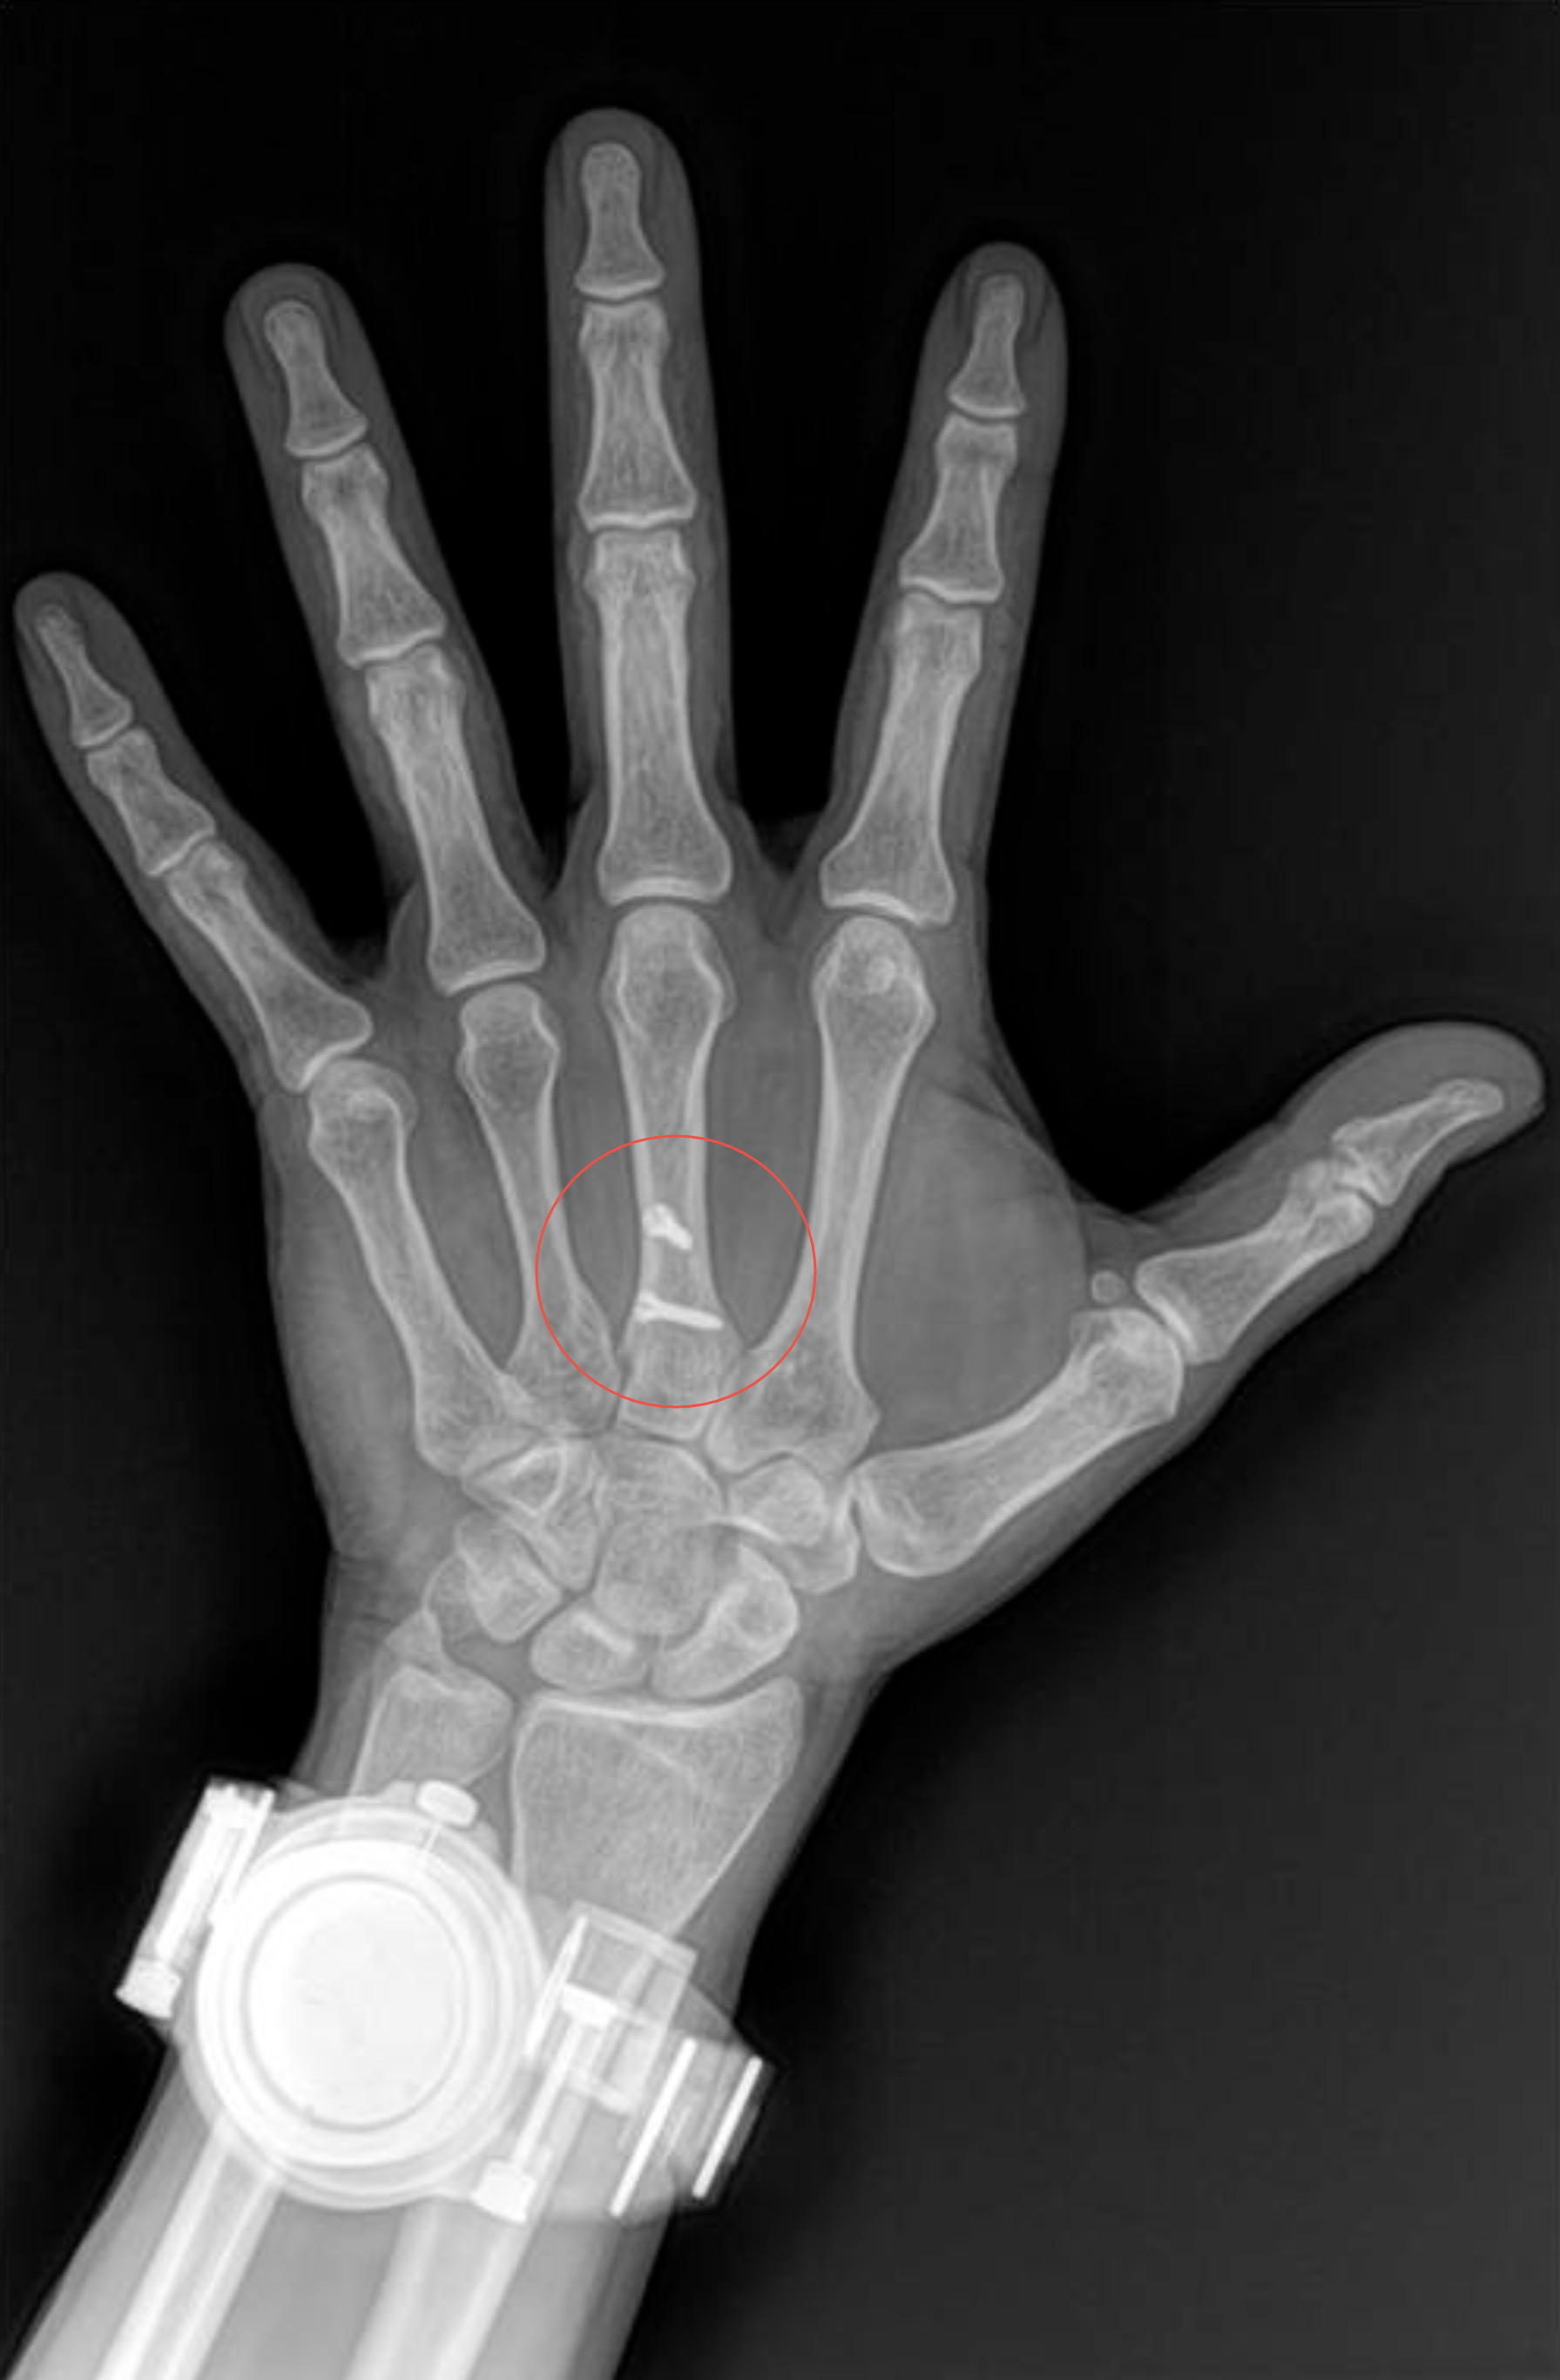

Radiología Digital como Herramienta Complementaria en el Dictamen de Bienes Muebles

Desde el descubrimiento de los rayos “X” y las placas radiográficas por Wilhelm Conrad Roentgen y su posterior difusión a través de la Asociación Físico médica de Wurzburg el 28 de diciembre de 1895, que fue la primera asociación que habló de los nuevos rayos que podían penetrar el cuerpo y fotografiar los huesos, ha habido muchos cambios tanto en la forma de obtener, procesar e incluso en la forma de visualizar, manejar y almacenar las placas radiográficas.